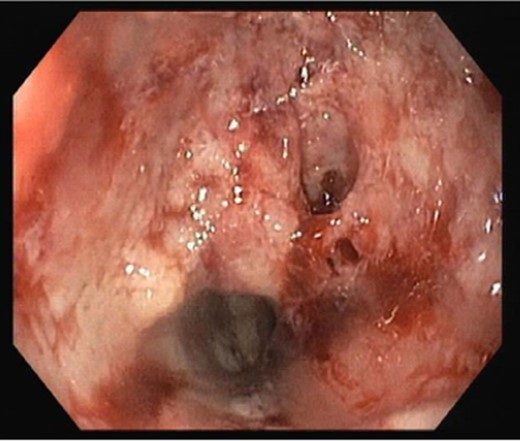

Upper digestive endoscopic study revealed an ulcerated vegetative neoplasia at 20 cm of the dental arch, insurmountable to endoscope (Fig. 1). A screening colonoscopy was unremarkable.